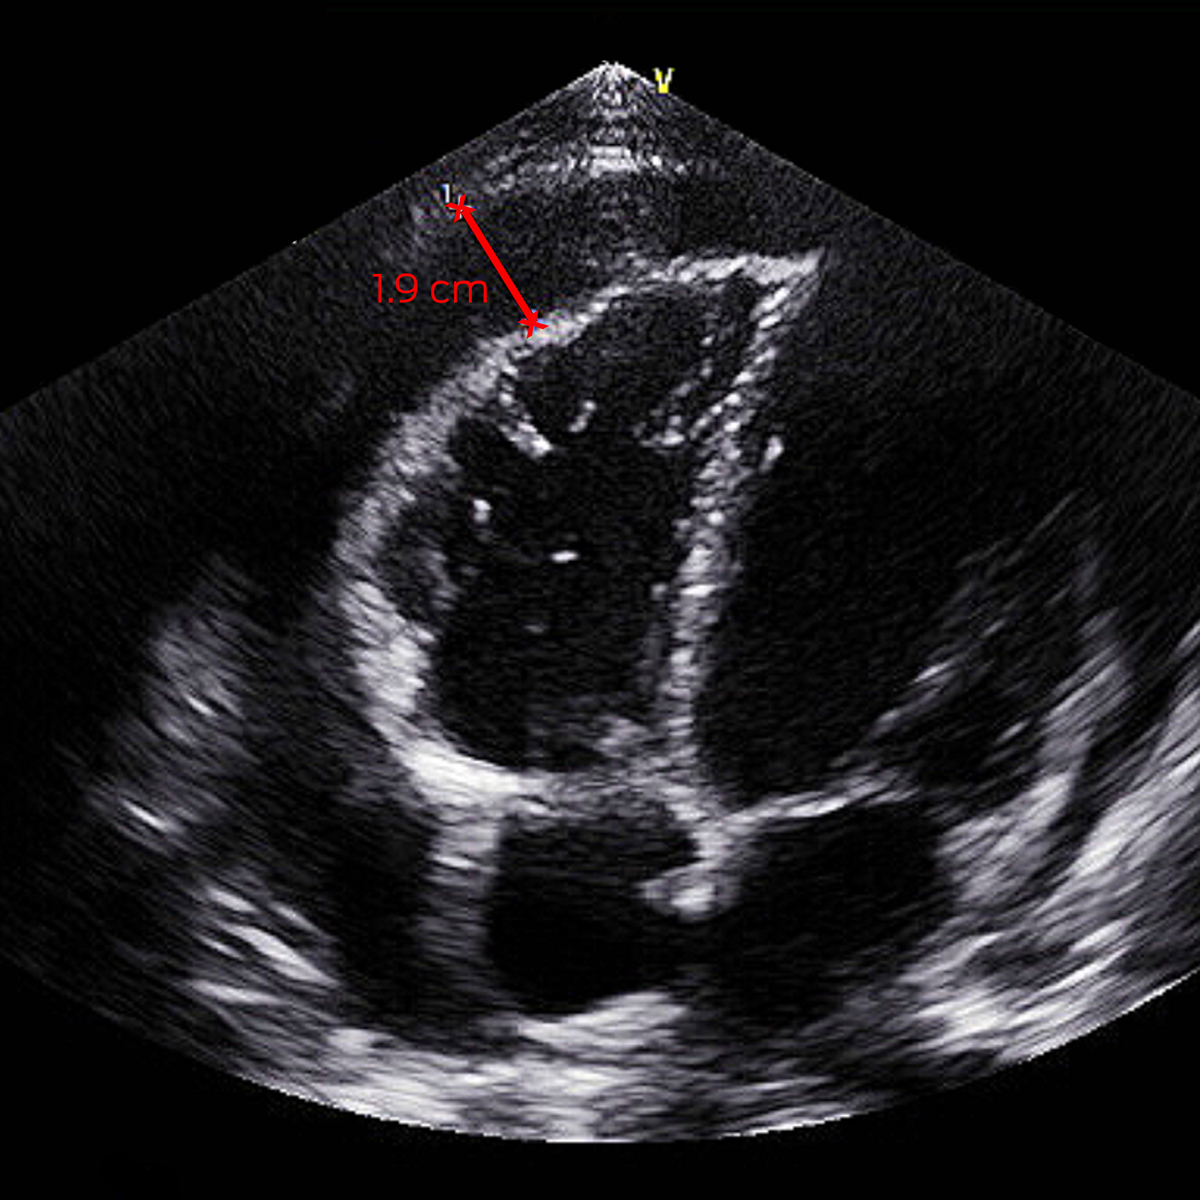

On day 5, his fevers recrudesced to 39°C with a new pericardial rub and anterior T‐wave flattening on electrocardiogram. Investigations demonstrated elevated troponin T 193 ng/L (RI, < 14 ng/L), CRP 65 mg/L, and total haemolytic complement > 1000 U/mL (RI, < 1000 U/mL). Septic screen was negative. Transthoracic echocardiography (TTE) showed a 0.5 cm pericardial effusion increasing to 1.9 cm (Box 1). He was treated for reactive meningococcal pericarditis with regular ibuprofen and colchicine, with resolution of fevers and improvement in inflammatory markers, and he was discharged five days later. He had negative human immunodeficiency virus (HIV) serology and normal complement studies after recovery. Minimal effusion on TTE by week 6 prompted transition to colchicine monotherapy, which was ceased at week 10.

Box 1 – Transthoracic echocardiogram off‐axis four chamber view with pericardial effusion measuring 1.9 cm